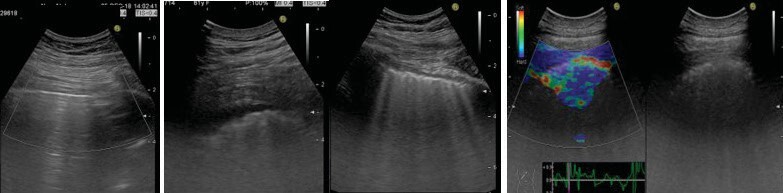

Introduction: Ultrasound elastography (US-E) is a novel, tissue stiffness-sensitive imaging method. We aimed to investigate whether lung ultrasound (US) and US-E can play a role in diagnosing interstitial lung diseases (ILDs) in which lung elasticity is affected due to fibrosis.

Materials and methods: A prospective cohort study. Patients with ILD were defined as ''ILD group'' and with other pulmonary diseases as ''control group". All subjects were examined and compared by lung US in B and elastography modes. Besides, the relationship between ultrasonography and high-resolution computerized tomography (HRCT) and chest X-ray findings was evaluated.

Result: A total of 109 patients, 55 in ILD and 54 in the control group, with a mean age of 62 ± 14 years, were included. A positive correlation was found between the Warrick score (calculated from HRCT to determine the severity of ILD) and the number of B-lines (discrete vertical reverberation artifacts, indicating interstitial lung syndrome) in lung US (p= 0.001, r= 0.550) in the ILD group. In US-E, blue color (meaning more rigid tissue) dominated in the ILD group, and green color (indicating medium tissue stiffness) dominated in the control group (p= 0.001). Lung US diagnosed the ILD with 69% accuracy, 80% sensitivity, and 60% specificity compared to HRCT. Combined with chest X-ray, diagnostic accuracy was 74%, sensitivity 60%, and specificity 89%.

Conclusions: Although lung US and US-E are not superior to gold standard HRCT in diagnosing ILDs, they can still be accepted as promising, novel, noninvasive tools, especially when combined with chest X-rays. Their role still needs to be clarified with further studies.